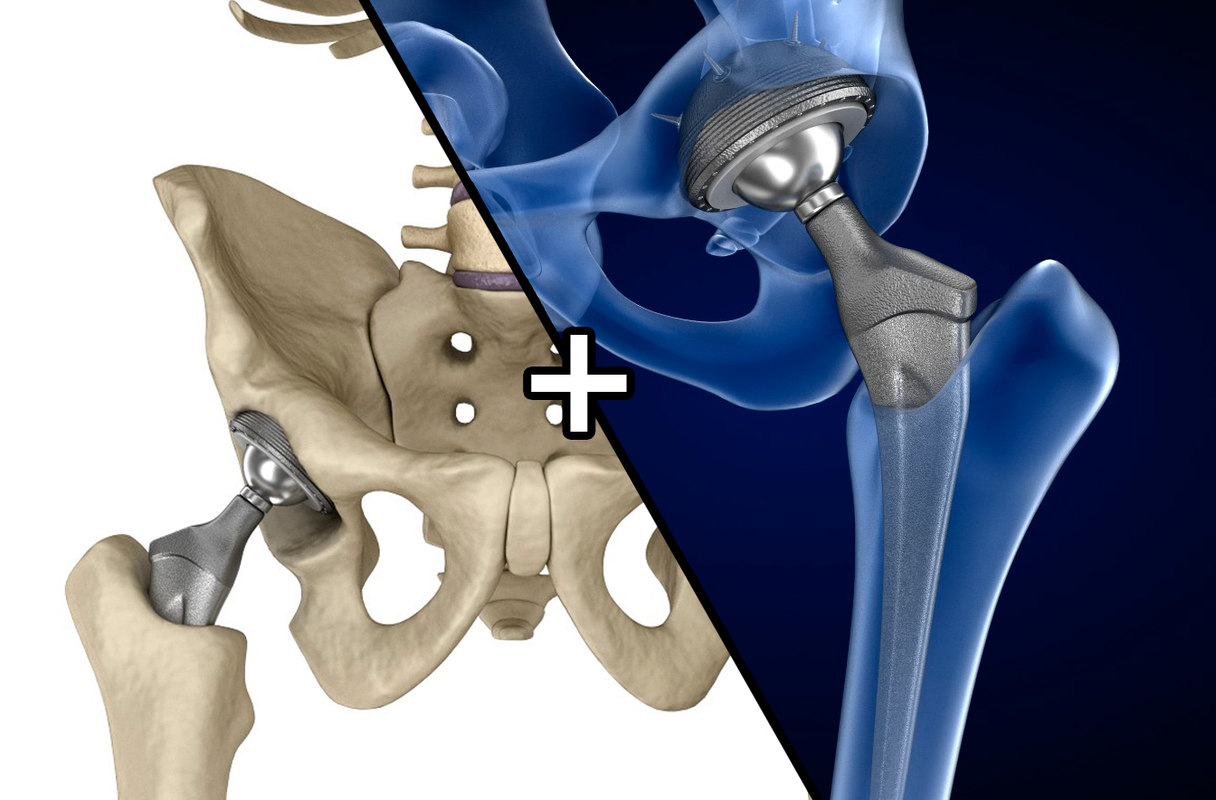

Hip Replacement With 3-D Printing And Stem Cell Graft | Medical

www.medicalautomation.org

www.medicalautomation.org

3D Hip Replacement Implant Installed Model - TurboSquid 1220758

www.turbosquid.com

www.turbosquid.com

hip 3d model replacement implant bone installed pelvis turbosquid